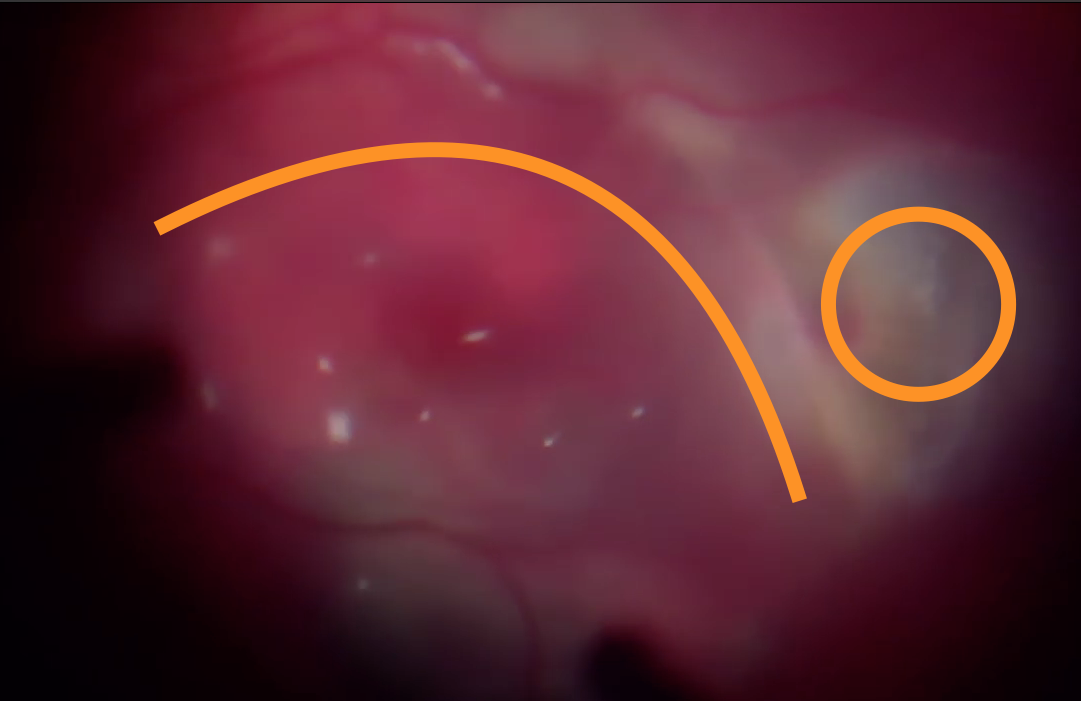

Об'єктивно - на правому оці субретинальний крововилив від аркади до аркади, з елементами субпігментного крововиливу, кров у стадії розсмоктування й у деяких ділянках фіброзування згустку.

Після діатермії було виконано дренуючу ретинотомію на межі крововиливу (можна було би ще ближче до центру, але не хотілося потім виконувати лезеркоагуляцію поблизу до СНМ) та частково роздреновано субретинальній простір.

Під час операції вдалося відмити значну частину субретинальної крові, що дає право сподіватися на збереження макулярних функцій, разом з цим, згорток крові, що знаходився під сітківкою протягом 3 тижнів, вже почав фіброзуватися - такі тяжі видалити не вдалося. Ми розраховуємо на те, що такі тяжі розташовуються ближче до аркад, тому на фовеолярні функції впливати не повинні.